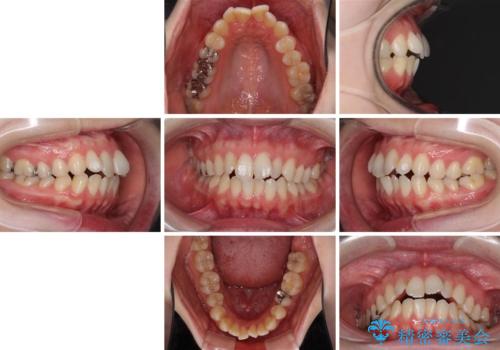

前歯のデコボコを改善 目立たないワイヤー矯正

- 前歯のデコボコを気にして来院された患者様です。

下顎が骨格的にずれており、上下正中を合わせることは難しいことが予想されたため、デコボコの解消を主目的として、ワイヤー矯正を行うこととしました。

治療途中で出産されたこともあり、当初予定よりも終了までに期間がかかってしまいました。

舌を前方に突出する癖があったため、上下前歯がなかなか接触しなかったことも治療期間が伸びた要因です。